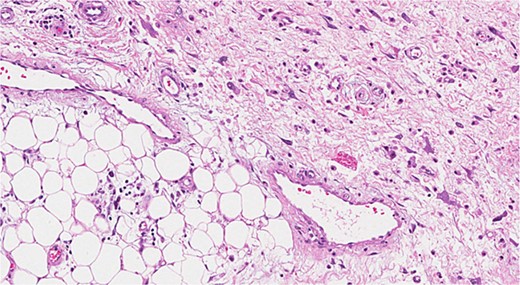

Histopathology (Fig. 3) reported a 40 × 27 × 17 cm encapsulated, high-grade (Grade III) dedifferentiated liposarcoma. No tumor proliferation was noted in the lymph nodes or adrenal gland. Postoperative recovery was uneventful, but the patient died after a year of chemotherapy due to respiratory distress.

Dedifferentiated liposarcoma. This image shows a high-grade tumor.